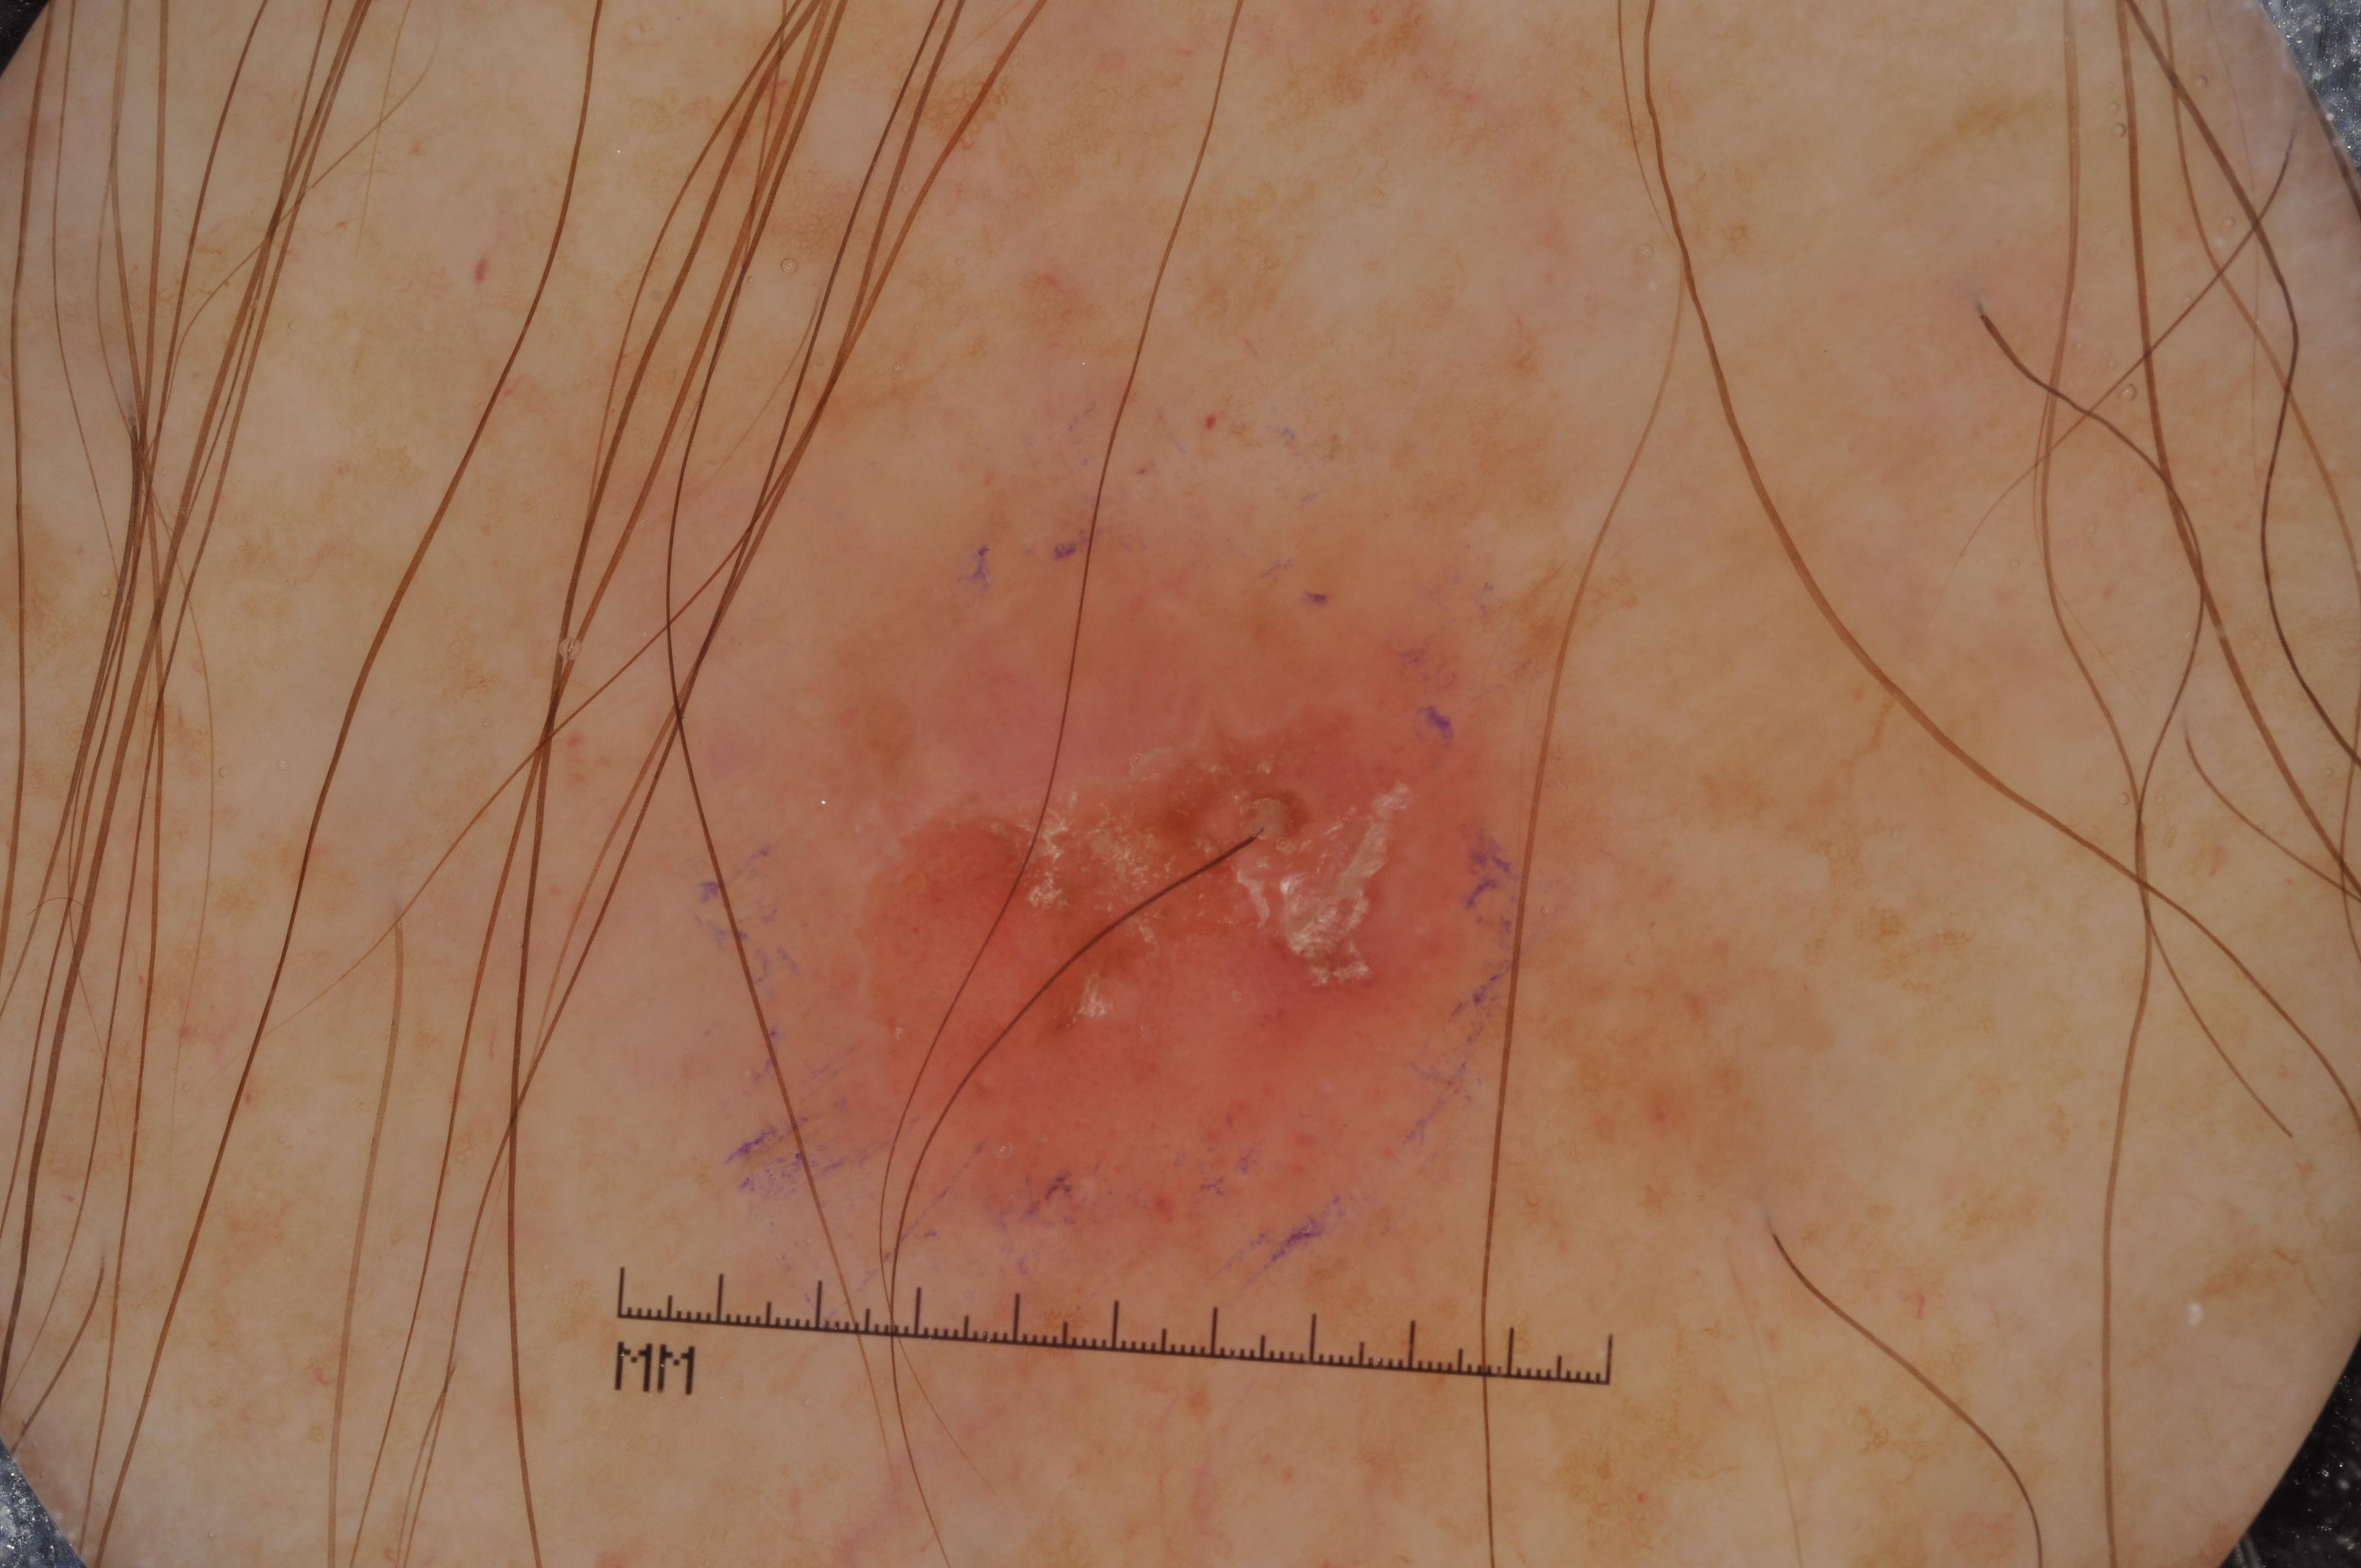

{

"age_approx": 65,

"anatom_site_general": "posterior torso",

"concomitant_biopsy": true,

"dermoscopic_type": "contact non-polarized",

"diagnosis_1": "Malignant",

"diagnosis_2": "Malignant melanocytic proliferations (Melanoma)",

"diagnosis_3": "Melanoma in situ",

"diagnosis_confirm_type": "histopathology",

"image_type": "dermoscopic",

"lesion_id": "IL_3704665",

"melanocytic": true,

"sex": "male"

}